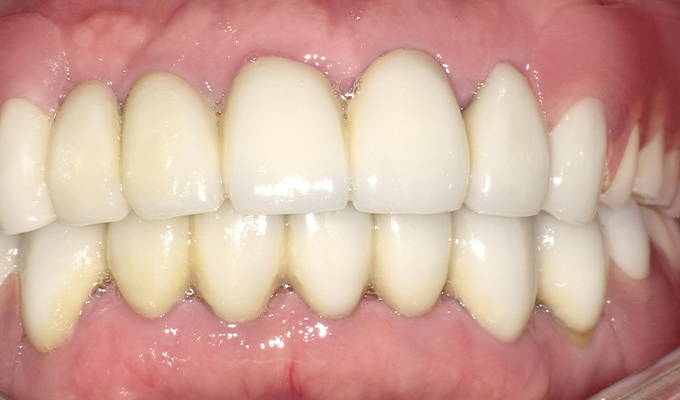

最新メンテナンス時(2023年)

- 上・・・虫歯の根だけの歯が数本残っているためすべて抜歯し仮義歯作成しました。最終的には8本インプラントを埋入し上部構造はメタルボンドです。

下・・・保存できる下の歯はメタルボンドブリッジにし、奥歯のない部分に3本インプラントを埋入しました。治療期間は2年ほどかかりましたがしっかり食事ができるようになったので嬉しいと、満足していただけました。

以降定期的にメンテナンスに来院いただき11年経過してもいい状態を維持されています。